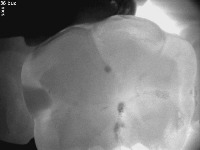

detect caries1 Computer Vision Project

Dental Diagnosis Assistance: This computer vision model can be used by dentists to quickly and accurately identify the presence of caries (decay) in patients' teeth during dental examinations, allowing for more efficient and targeted treatment plans.

Dental Insurance Claims Verification: Insurance companies can utilize the model to review submitted dental claims, validating the presence of caries and other dental issues, helping to reduce instances of insurance fraud and streamlining the claim approval process.